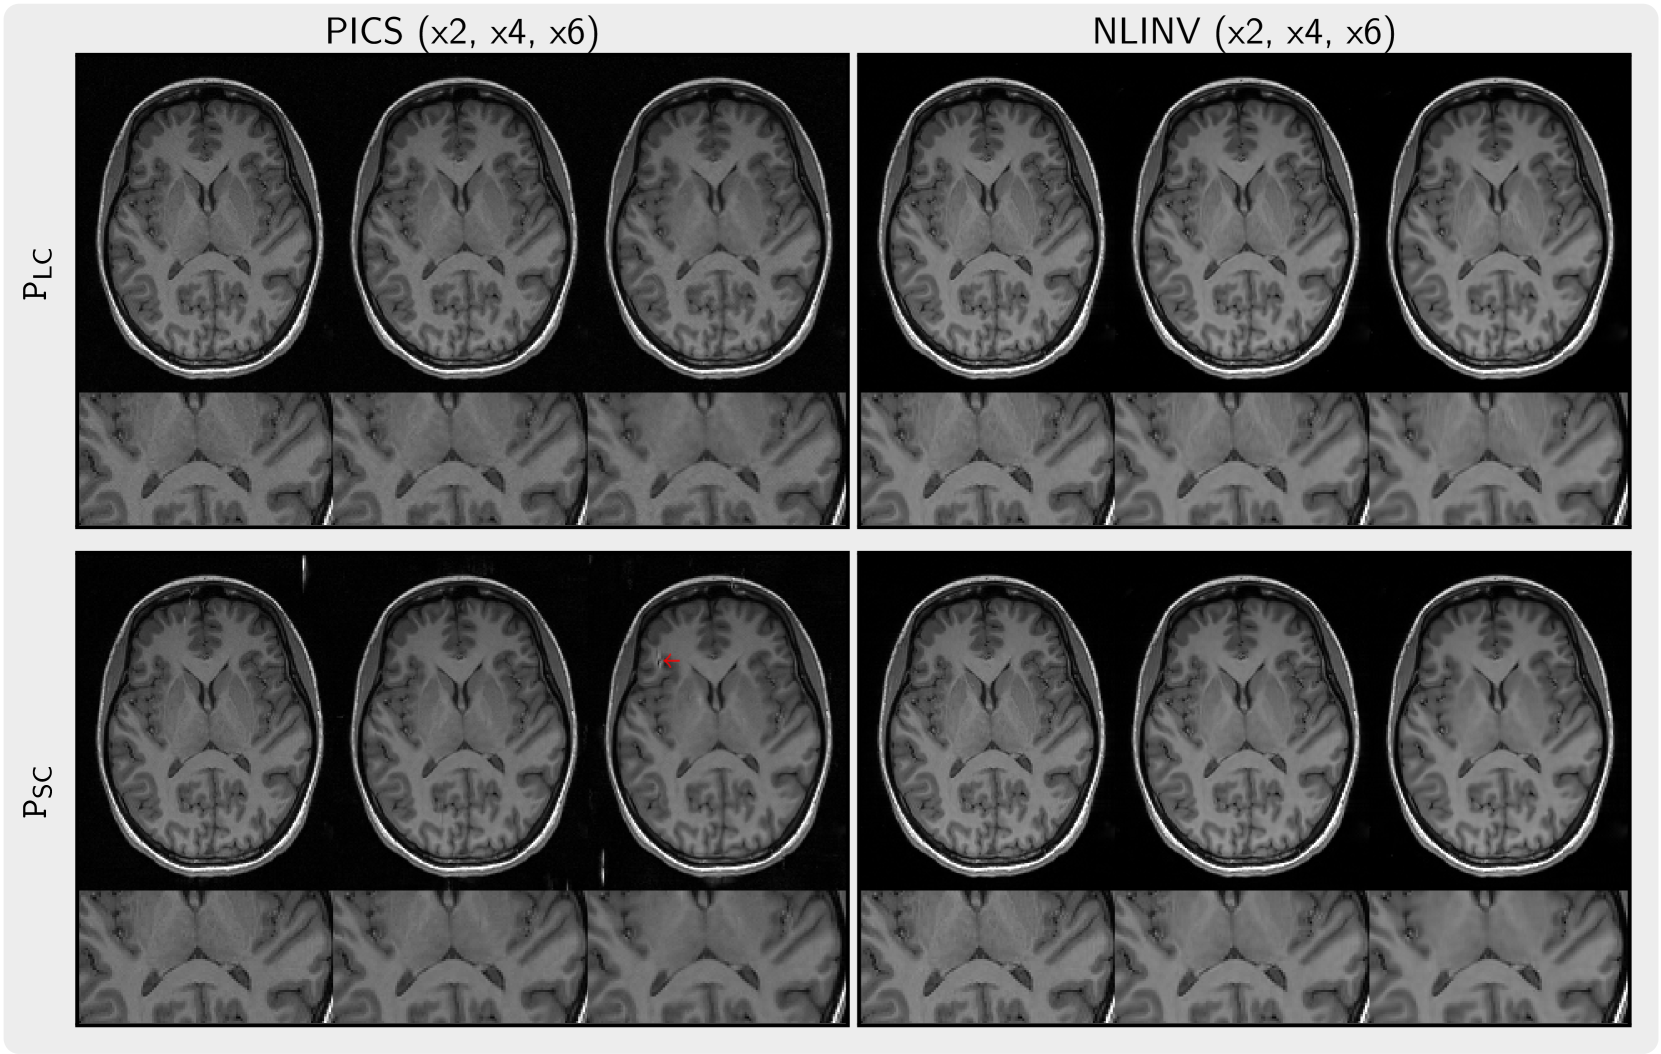

Figure 6 presents the images regularized by the priors (PSC and PLC) trained on small and large datasets, respectively. When using PICS with the prior PSC artifacts become apparent in the background and in the brain, whereas no such artifacts are observed when applying the prior PLC. Furthermore, image details appear to be better preserved with high undersampling for the prior PLC.

Refer to caption

Figure 6: Comparison of images reconstructed with PICS (left) and NLINV (right) using priors PLC (top) and PSC (bottom) trained on small and large datasets. We observed artifacts (red arrow) when using PICS with the prior PSC trained on the small dataset. The images in each column are reconstructed from k-space undersampled with factors ranging from 2 to 6 (left to right).